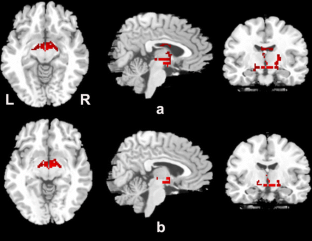

White matter deficits constitute one element of the network dysfunction that underlies progressive supranuclear palsy (PSP). Cumulative evidence of white matter abnormalities in patients with PSP has been reported using voxel-based morphometry (VBM), but these studies have not been quantitatively reviewed and not all findings have been entirely concordant. Whole-brain VBM studies comparing PSP patients with healthy controls (HC) were systematically searched in the PubMed and EMABSE databases from January 1990 to April 2013. Coordinates with significant differences in the white matter volume (WMV) between PSP patients and HC were extracted from each cluster. A meta-analysis was performed using anatomic likelihood estimation. Ten studies with a total of 159 PSP patients and 236 HC were included in the meta-analysis. WMV reductions were observed in the midbrain, pons and the regions close to the basal ganglia. No WMV increase was reported. Meta-regression showed both MMSE and UPDRS III scores correlated with WM changes in the regions from bilateral midbrain to basal ganglia. Our findings provide evidence for white matter atrophy in the midbrain, pons and several regions near the basal ganglia, representing the main pathophysiology of PSP.

Fig. 1

Fig. 2